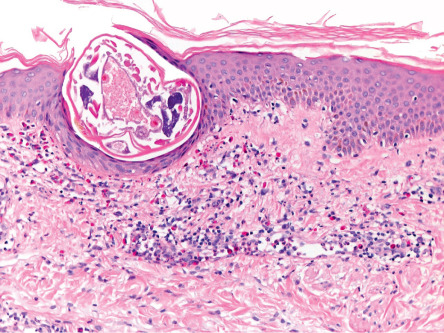

Pathology

A patchy to diffuse infiltrate with prominent eosinophils as well as lymphocytes and histiocytes is noted in the reticular dermis. A transected scabies mite may occasionally be seen within the epidermis ( Fig. 84.6 ). Pink “pigtail”-like structures attached to the stratum corneum, which represent fragments of the adult mite exoskeleton, can serve as a clue to the diagnosis of scabies when entire mites, scybala, and eggs are not identified .